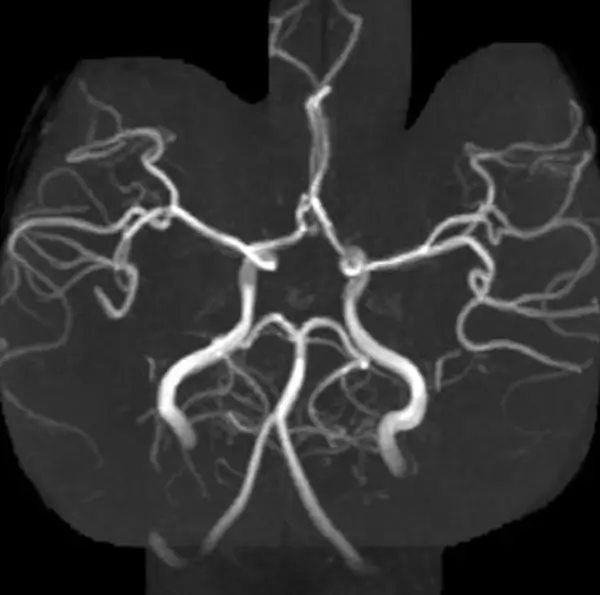

An MR Angiography of Intracranial Vessels is a test of the head in which the blood vessels leading to the brain are examined to check for a bulge (aneurysm), a clot, or a narrowing (stenosis) because of plaque.

MR Angiography of Intracranial Vessels is a procedure that uses a magnetic field, radio waves and a computer to create detailed images of the blood vessels leading to the brain. The test distinguishes normal, healthy tissue from diseased tissue.

MR Angiography for Intracranial Vessels is a Magnetic Resonance Imaging non-invasive medical diagnostic tool that is used to look for abnormalities in the vessels of the head leading to the brain.